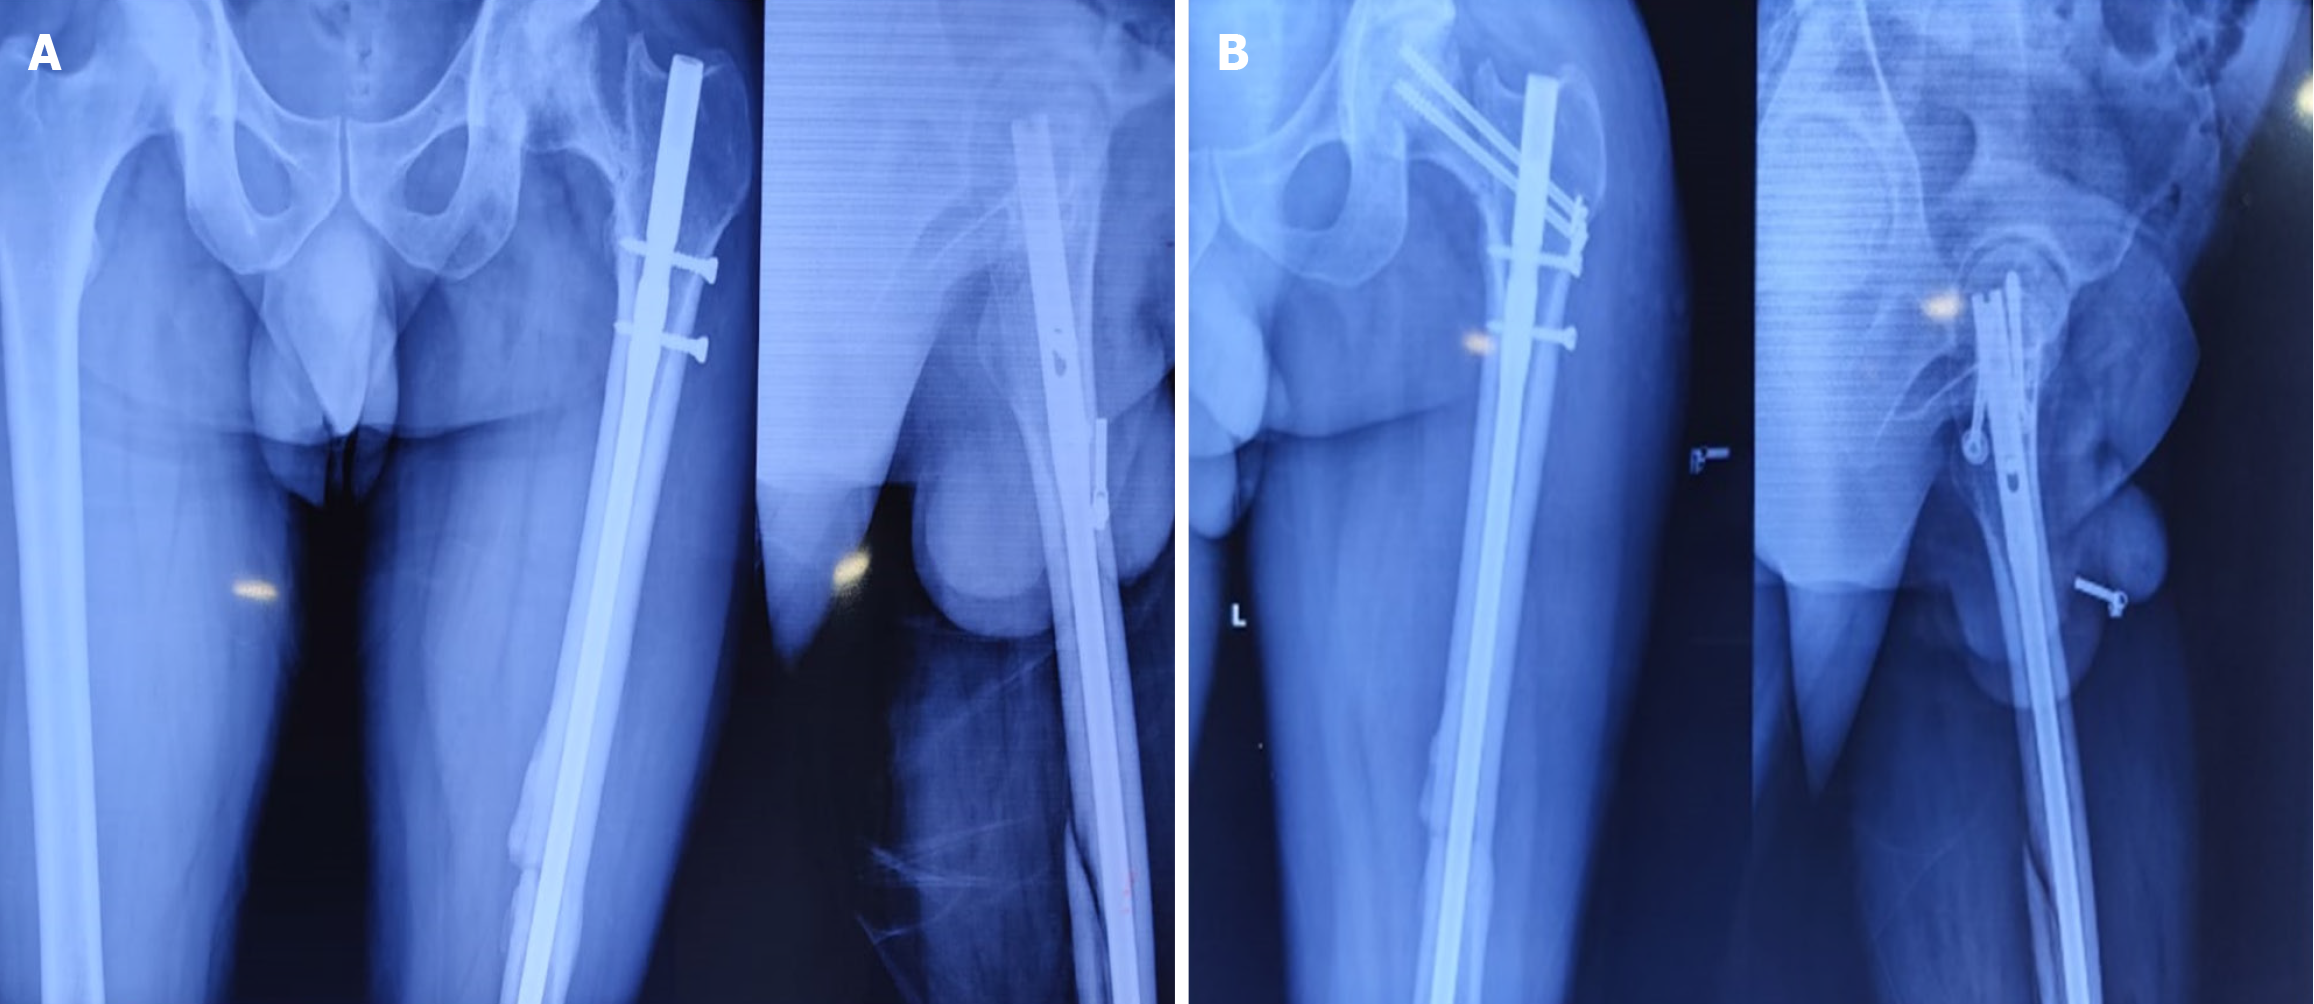

Fractures were diagnosed intraoperatively in 14 cases, immediately postoperatively in 1 case, and during follow-up (within 4 weeks) in 3 cases. The etiological breakdown included erroneous entry point (6 cases) as shown in Figure 3, inadvertent jig hammering (5 cases) as shown in Figure 4, misdirected nail manipulation (3 cases), hoop stress-related fractures (3 cases) as shown in Figure 5, and one case of unexplained origin. Intraoperative fractures were typically identified during final fluoroscopic checks, while postoperative fractures were detected on follow-up radiographs without intervening trauma Figure 6. The list of eitiologies contributing to iatrogenic fractures during femoral nailing is listed in Table 1.

| Erroneous entry point | 6 | Intraoperative | 4 undisplaced, 2 displaced | Long PFN (5), CCS (1) |

| Inadvertent jig hammering | 5 | Intraoperative | 3 undisplaced, 2 displaced | Long PFN (3), CCS (2) |

| Misdirected nail manipulation | 3 | Intraoperative | 2 undisplaced, 1 displaced | Long PFN (2), CCS (1) |